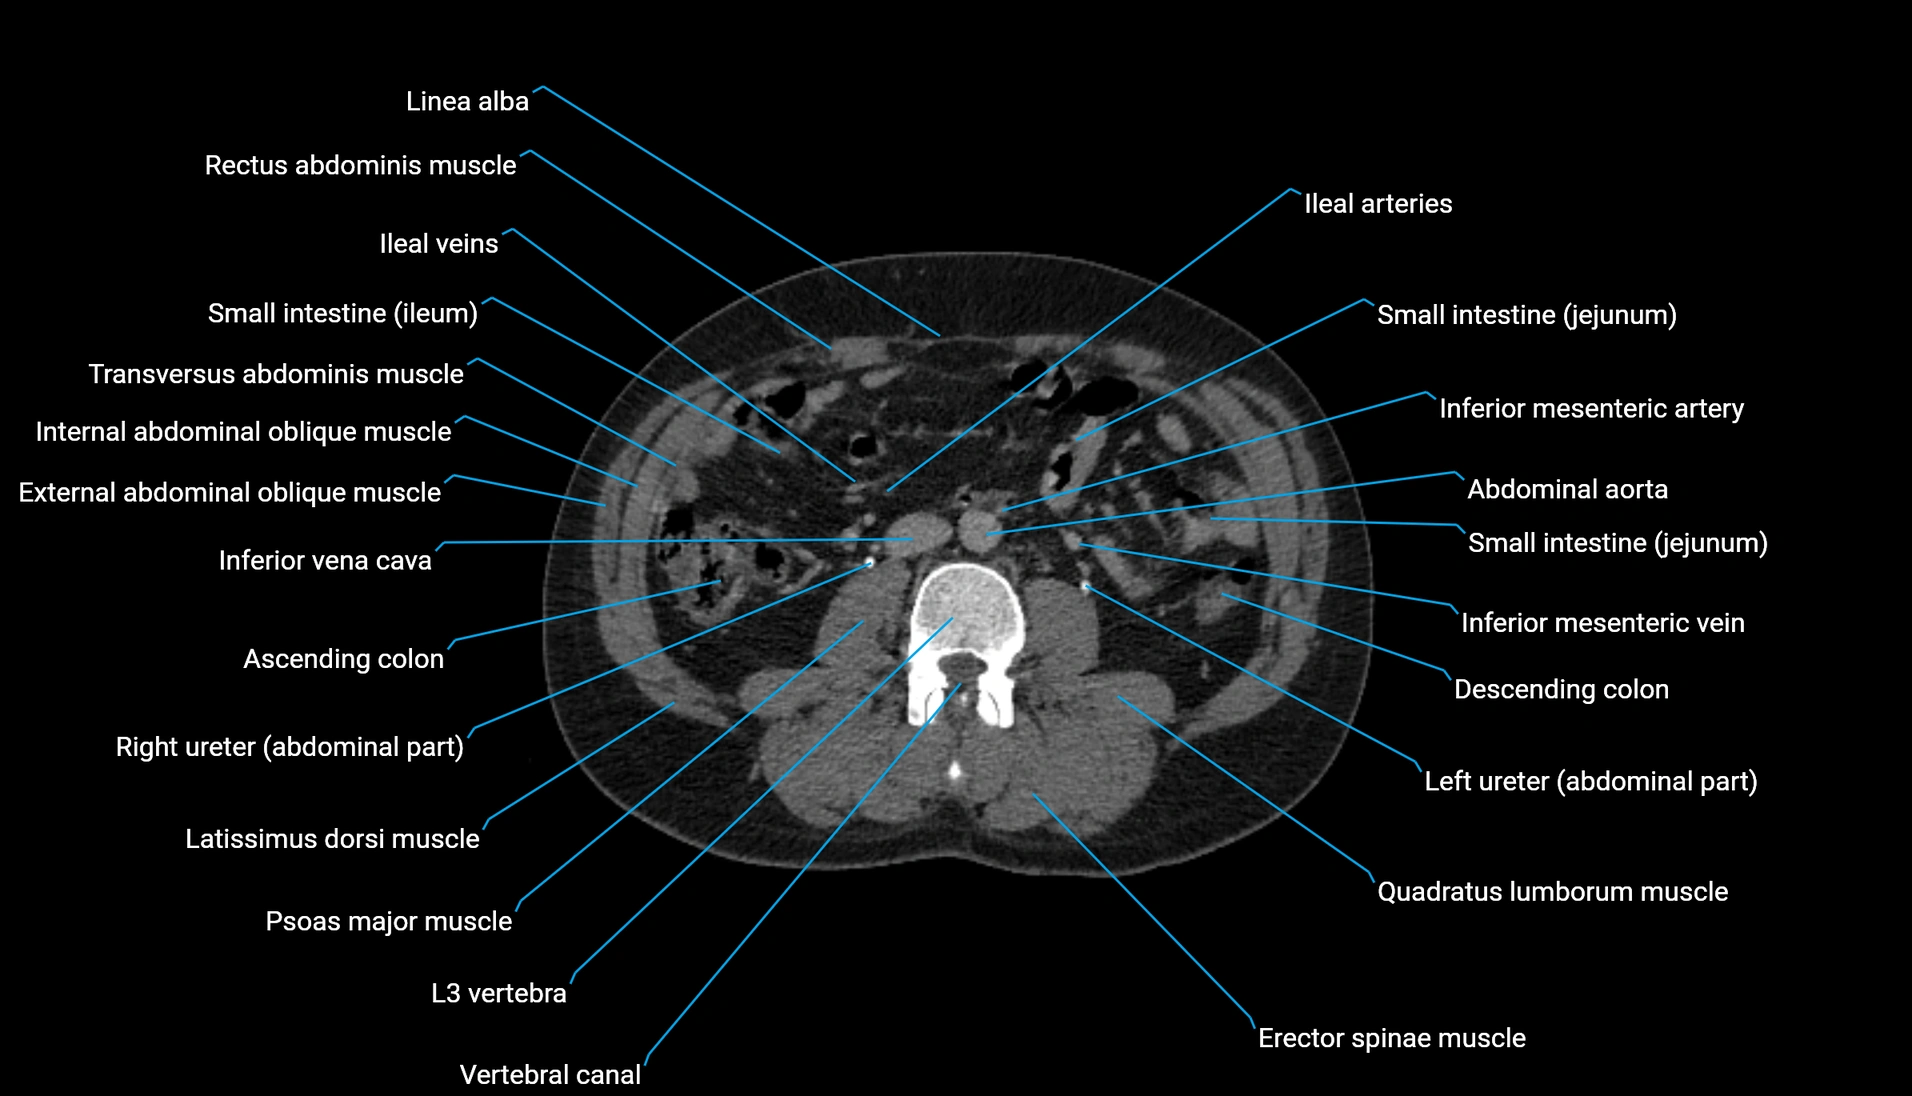

CT Appearance

Non-contrast CT:

-

Demonstrates cortical bone of acetabular rim in excellent detail

Detects fractures, dysplasia, retroversion, or bony overcoverage (pincer impingement)

3D reconstructions used in preoperative hip surgery planning

CT VRT 3D image

CT image